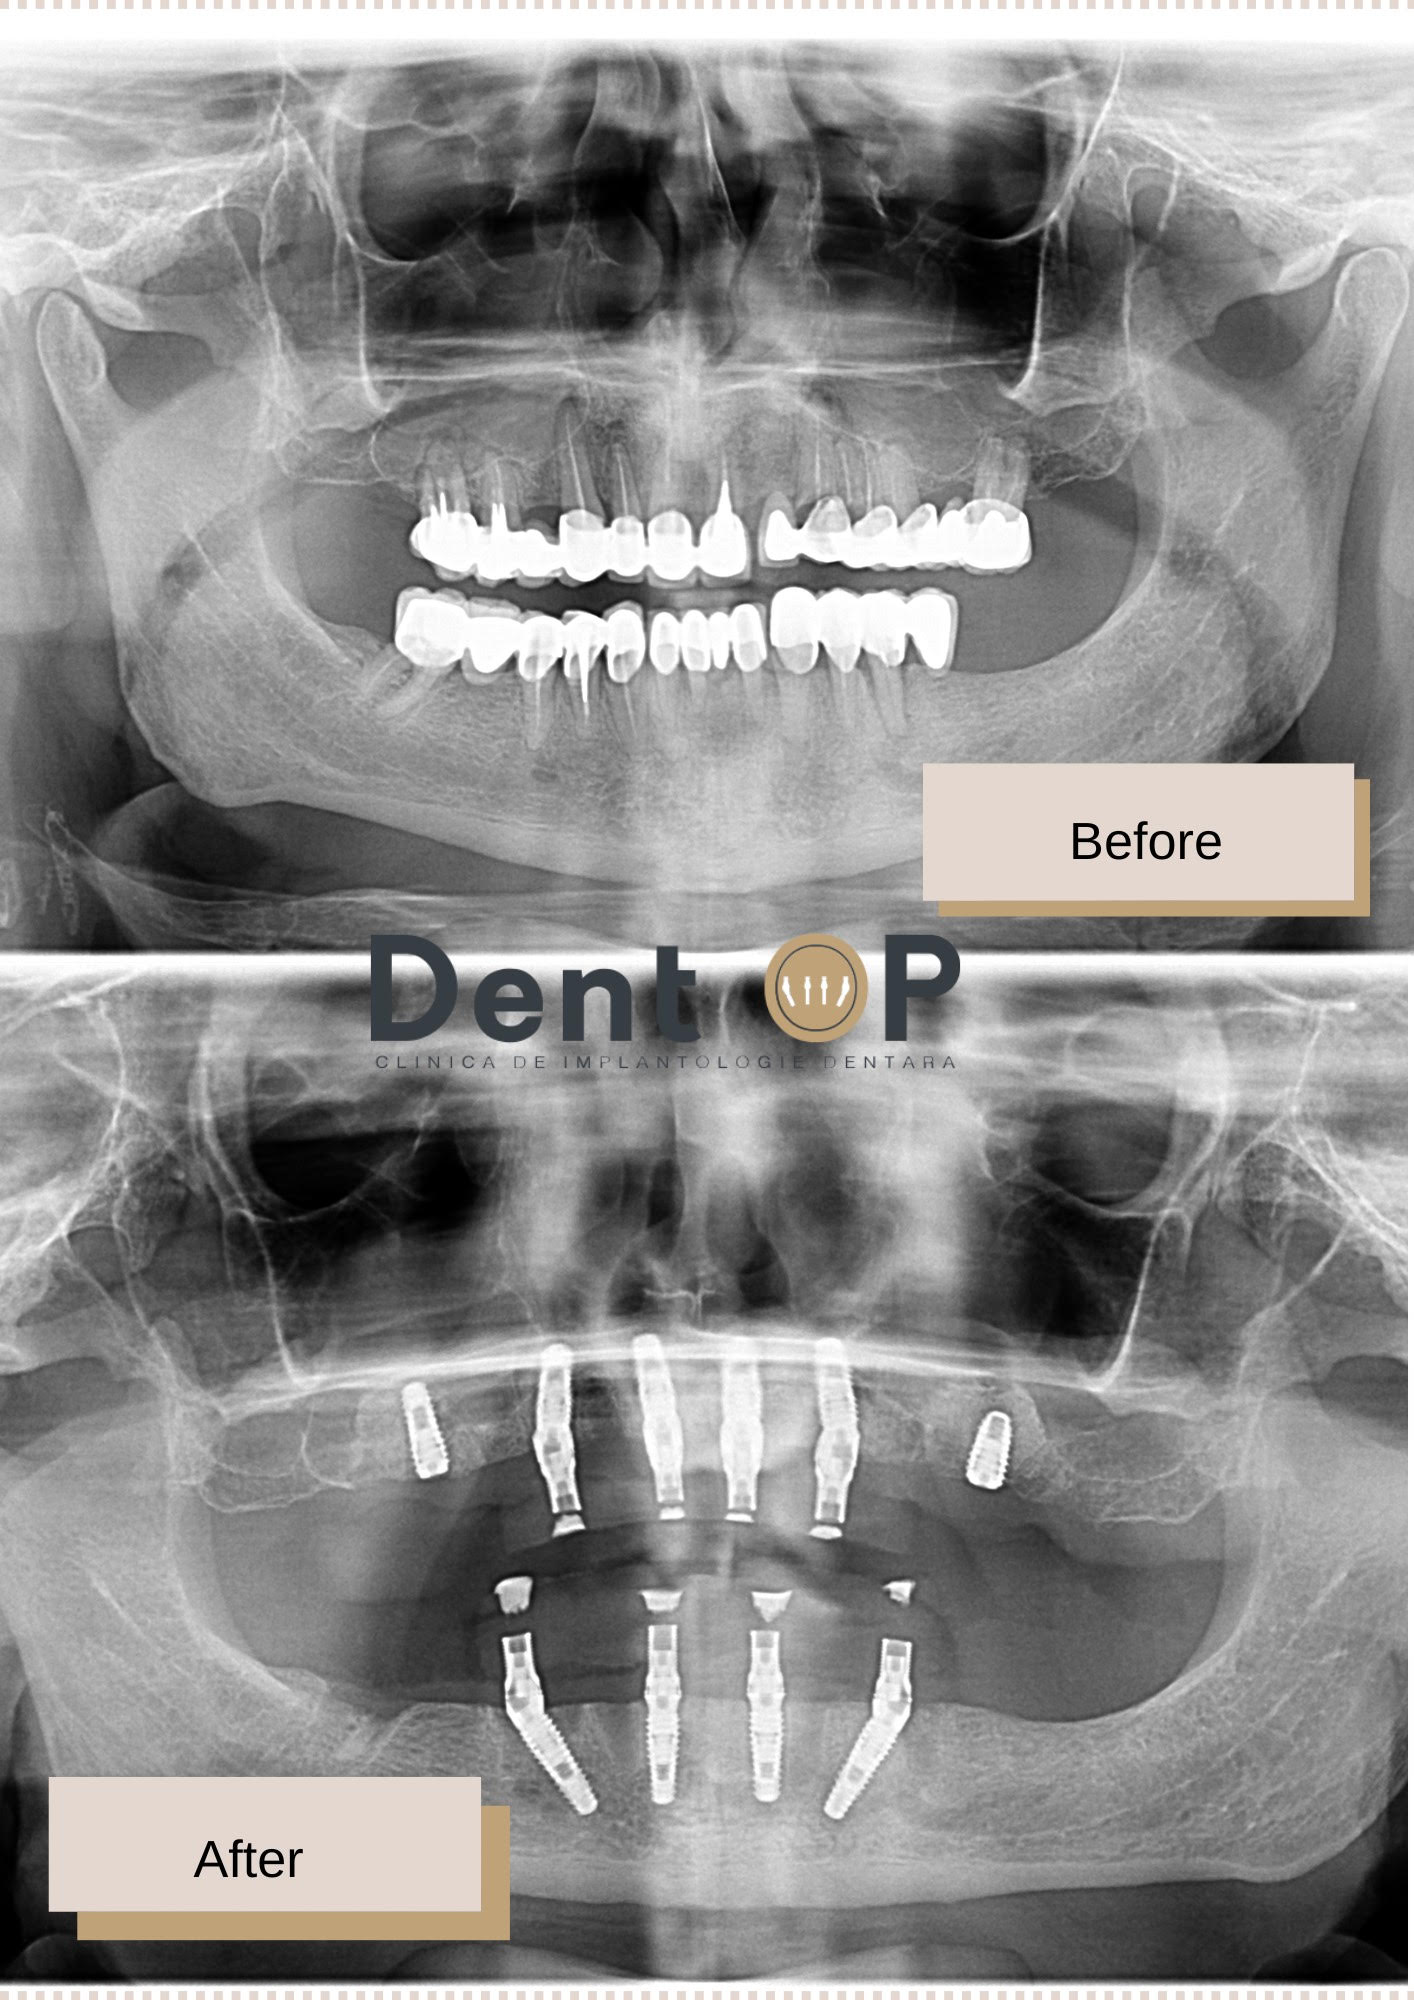

Domnul D. este unul dintre pacienții care a venit la noi cu dantura afectată de această boală, iar dantura sa nu a putut fi salvată. Când a ajuns în cadrul consultației cu Dr Cazacu Corrado, Medicul Specialist în Chirurgie Dento-Alveolară i-a propus un plan de tratament personalizat, care l-a ajutat să-și recapete zâmbetul în doar 24h.

I-au fost inserate 10 implanturi dentare, 6 la maxilar și 4 la mandibulă într-o singură ședință cu Sedare Conștientă. Cu ajutorul lucrării provizorii inserate chiar din a doua zi, pacientul a primit și dantura care l-a ajutat timp de 6 luni să aibă dinți ficși.